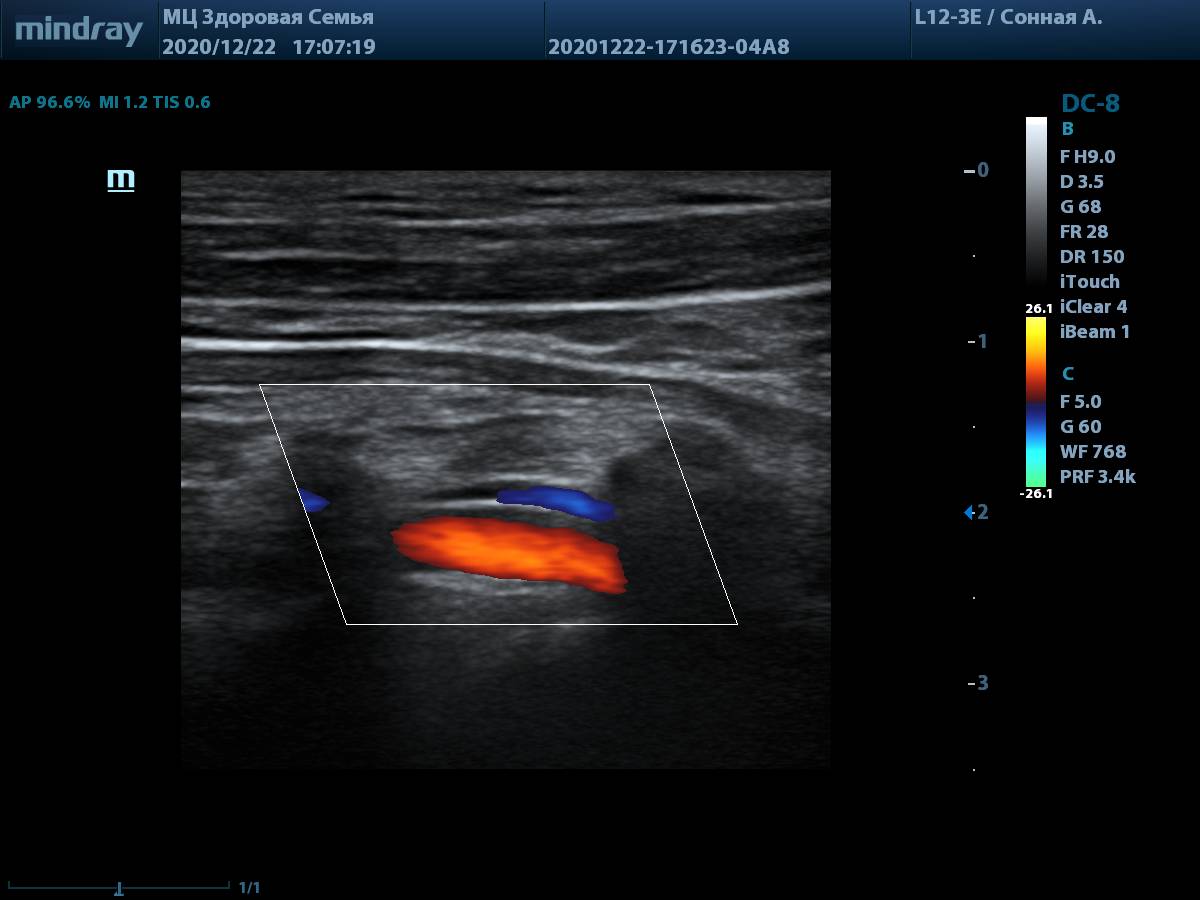

7. Линейный датчик L12-3E, оценка глубоких структур, таких как позвоночная артерия, не вызывает трудностей. Хорошая чувствительность цветового допплера на глубине.